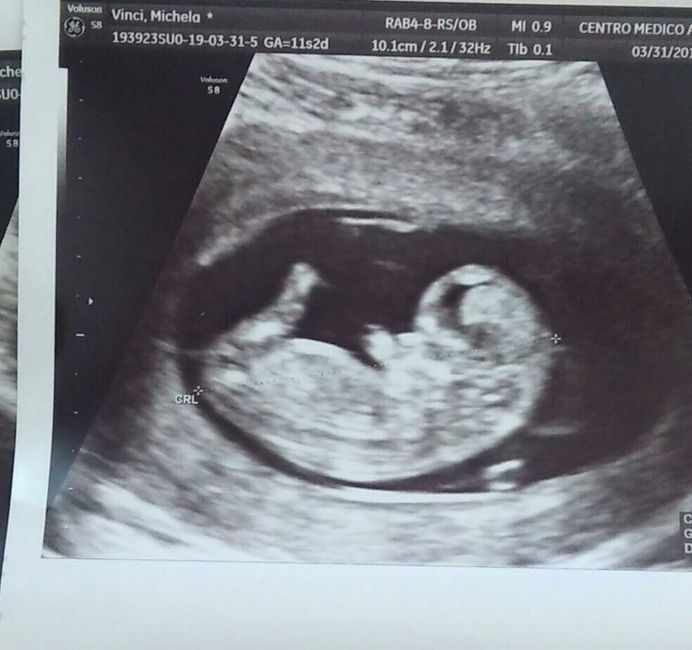

Eccolo a 11 settimane 😍 ora sono di 14 domani..la seconda foto è il suo sederino 😁 a me e anche mio marito pare di vedere un piccolo pistolino 😄 secondo voi cos'è? Devo aspettare fine maggio inizi giugno x scoprirlo uff

Questo era il mio cucciolo a 11 settimane.. il pisellino era molto più evidente...tieni presente che in quella fase maschi e femmine hanno la stessa piccola protuberanza..

Di maschietto non vedo nulla oltretutto il sesso si completa a 12/14 sett.

Se avesse il pisellino si vedrebbe bene